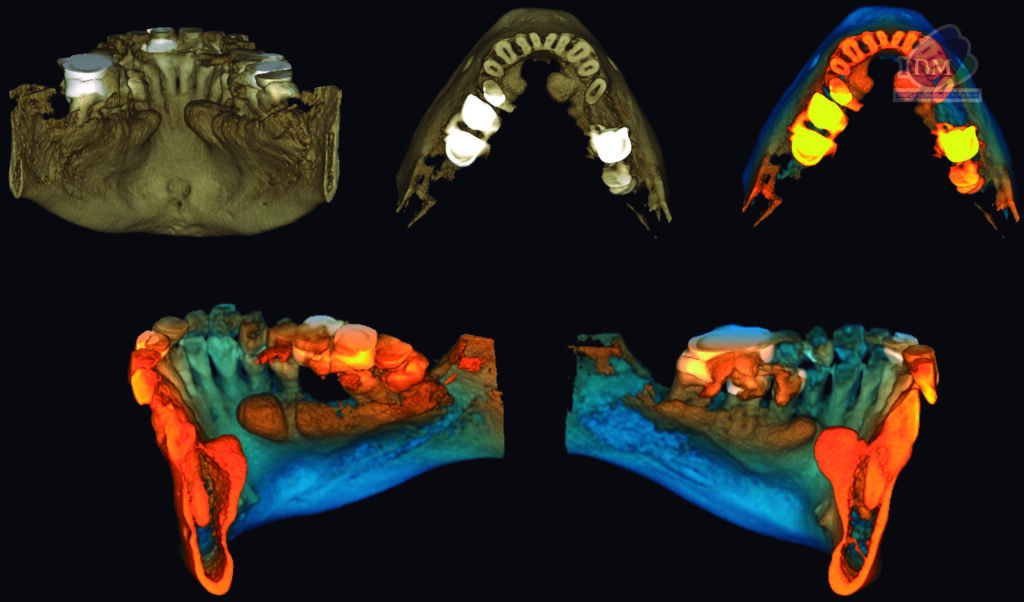

A la evaluación de la tomografía computarizada bimaxilar se observó además de los mencionado, la presencia de imágenes hiperdensas de densidad dentaria de forma irregular ubicadas por lingual, en estrecha relación con la tabla ósea y a nivel de las piezas 34-35 y 44-45 compatibles con torus mandibular.

RECONSTRUCCIÓN 3D